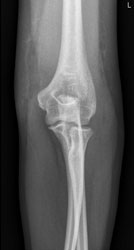

Eine 37 Jahre alte Frau stürzt auf dem Eis zu Boden und stützt sich mit dem linken Arm noch ab. Wegen Schmerzen im linken Ellbogen geht sie zum Arzt, welcher das folgende Röntgenbild macht.

Der erstbehandelnde Arzt sieht auf dem Röntgenbild keine Fraktur und verordnet der Patientin Schmerzmittel. Weil die Schmerzen aber nicht bessern, meldet sich die Patientin wieder und das Röntgenbild wird noch einmal beurteilt: